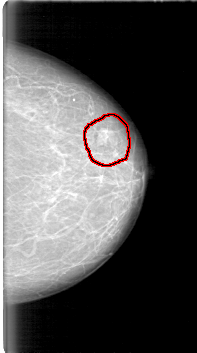

D_4091_1.RIGHT_MLO

FILE: D_4091_1.LEFT_MLO.OVERLAY

TOTAL_ABNORMALITIES 1

ABNORMALITY 1

LESION_TYPE MASS SHAPE LOBULATED MARGINS OBSCURED

ASSESSMENT 0

SUBTLETY 5

PATHOLOGY BENIGN

TOTAL_OUTLINES 1

BOUNDARY